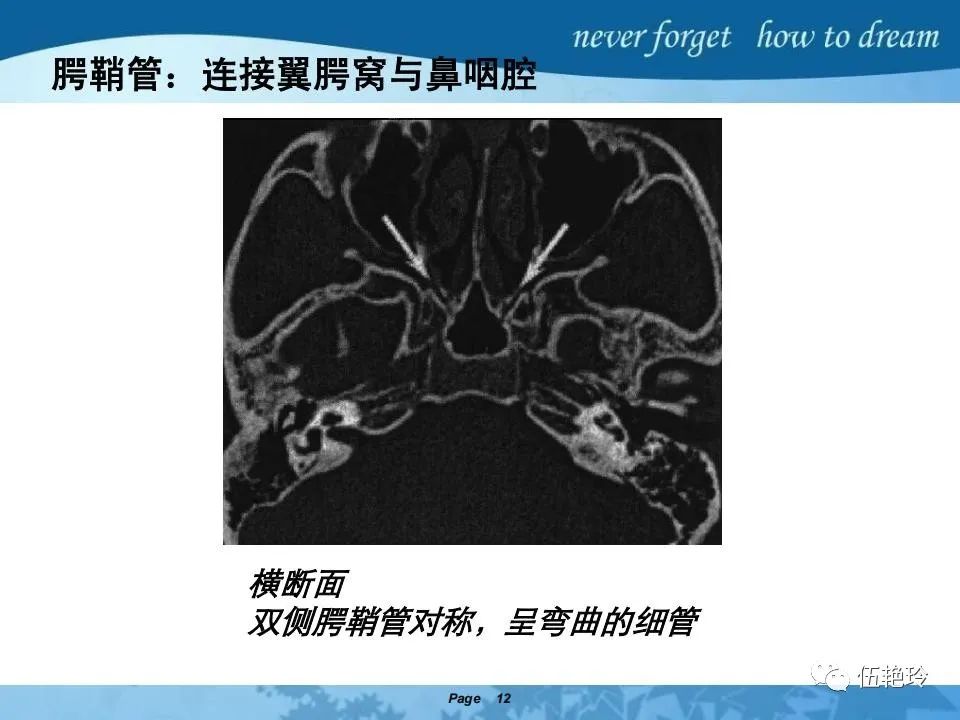

翼腭窝的解剖结构与鼻咽癌侵犯